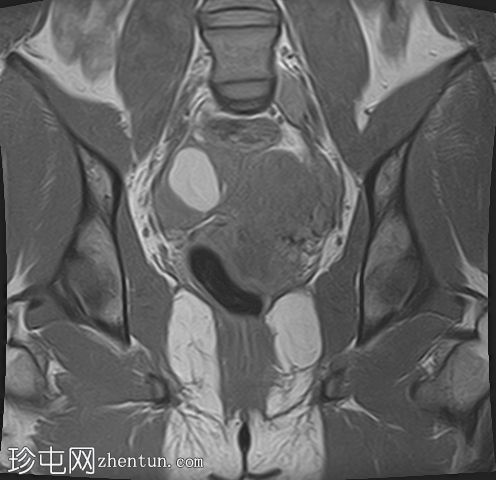

冠状位

T2加权像

在右侧附件区可见一较大病灶,最大轴位和头尾径约为3 x 3.8 x 3.7 cm。该病灶在T1加权像上呈高信号,脂肪抑制像上无信号抑制,在T2加权像上呈低信号(阴影效应)。病灶壁可见T2暗点征结节,增强扫描后未见明显强化。

右侧附件区可见两个较小的类似病灶,最大径约1.2 cm。

此外,右侧附件区可见一扩张的管状结构,最大轴向和头尾径约6.3 x 2.1 x 5.2 cm。

该结构T1呈低至中等信号,T2呈高信号,分隔不完整。增强扫描未见明显强化,符合输卵管积水表现。

双侧卵巢呈多囊性形态,优势卵泡保留。符合多囊卵巢(PCO)的影像学表现,T2加权像呈高信号,T1加权像呈低信号,并可见薄壁强化。

所描述的右侧附件病灶具有典型的子宫内膜异位囊肿MRI特征,包括T1高信号(无脂肪抑制)和T2低信号(阴影)。T2暗点征的存在进一步支持慢性出血性内容物。

相关的较小病灶可能代表其他子宫内膜异位种植灶。

扩张的管状结构伴有T2高信号和不完全分隔,符合输卵管积水的表现,输卵管积水常见于盆腔子宫内膜异位症。少量邻近游离液体通常为反应性积液。